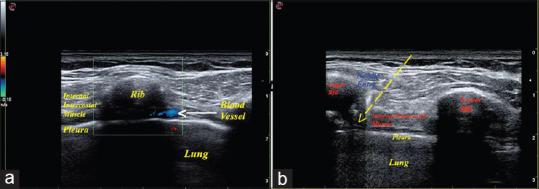

Patients were randomized into two groups. Patients in the parasternal intercostal block group (PIB) ( = 45) received ultrasound-guided modified parasternal intercostal nerve block with 0.5% levobupivacaine after anesthesia induction at 2-6 intercostal space along postinduction using standardized anesthesia drugs with routine postoperative hospital analgesic protocol with intravenous morphine. Patients in the group following routine hospital analgesia protocol (HAP) ( = 45) served as controls, with standardized anesthesia drugs and routine hospital postoperative analgesic protocol with intravenous morphine. The primary study outcome aimed to evaluate pain at rest and when doing deep breathing exercises with spirometry, coughing expectorations using a 11-point numerical rating scale.

将患者随机分为两组。胸骨旁肋间阻滞组(PIB组)(n = 45)在麻醉诱导后,于第2 - 6肋间间隙使用0.5%左旋布比卡因进行超声引导下改良胸骨旁肋间神经阻滞,使用标准化麻醉药物,并采用常规术后院内镇痛方案,静脉注射吗啡。常规院内镇痛方案组(HAP组)(n = 45)作为对照组,使用标准化麻醉药物和常规术后院内镇痛方案,静脉注射吗啡。主要研究结局旨在使用11分数字评分量表评估静息时以及进行肺活量测定深呼吸练习、咳嗽咳痰时的疼痛程度。